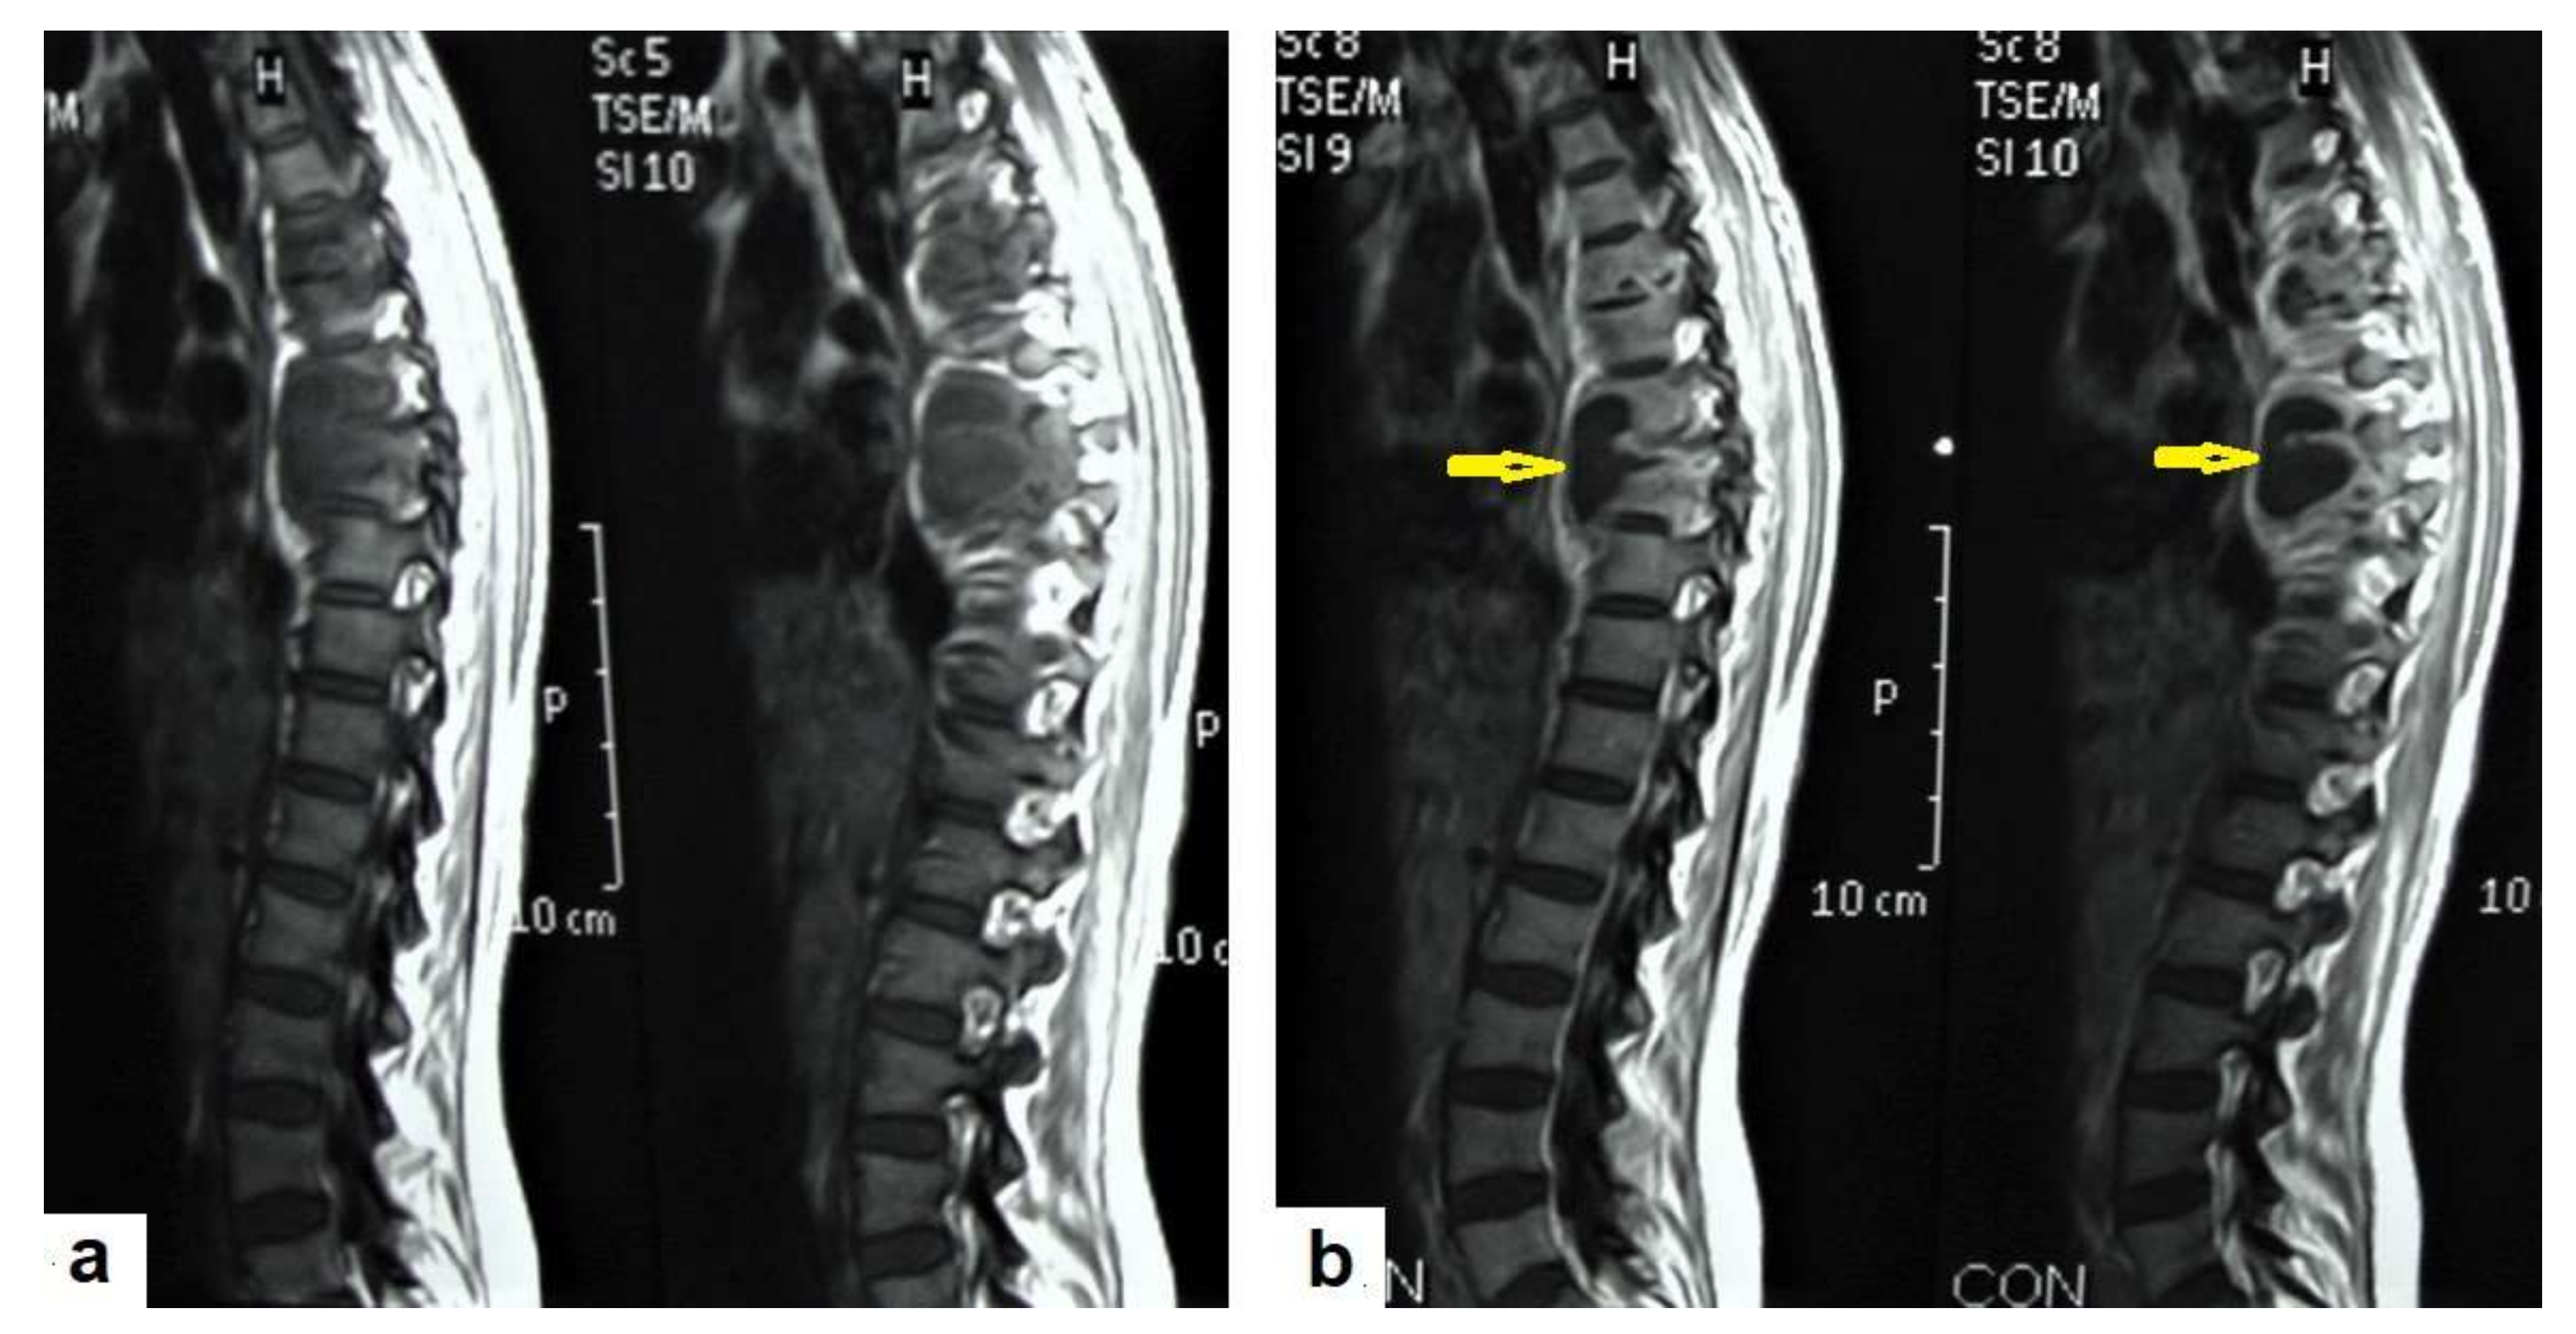

• Tuberculous spondylitis (Pott’s disease; Figure 18 and Figure 19) is a tuberculous infection of the spine that can affect any age and most commonly affects the lower thoracic and lumbar, followed by the cervical spine. It usually affects multiple contiguous vertebrae with paraspinal extension, causing subdural or epidural abscess formation and resultant spinal cord compression, which is a leading cause of paraplegia [27]. CT demonstrates the extent of bone involvement, while MRI demonstrates spinal-cord and soft-tissue involvement. Tuberculous spondylitis appears as a well-defined paraspinal abnormal signal intensity, as a thin wall abscess, or a combination of intraosseous and soft tissue abscesses. The spread of infection is sub-ligamentous beneath the anterior longitudinal ligament involving multiple vertebrae with high signal intensity on T2WIs. Pott’s disease is a difficult differential diagnosis with a spinal pyogenic infection. MRI demonstrate have 100% sensitivity, 80% specificity, and 90% accuracy in differentiating tuberculous from pyogenic spinal infection [34].

Figure 18. Pott’s disease in a 28-year-old female. Selected images of sagittal MRI of thoracic spine show destructive lesion affects multiple contiguous thoracic vertebrae with paraspinal collection. (a) Pre-contrast and (b) post-contrast T1-weighted images show subligamentous spread of the infection to involve five vertebrae with peripheral enhancement of the lesions, suggesting an abscess (arrow).